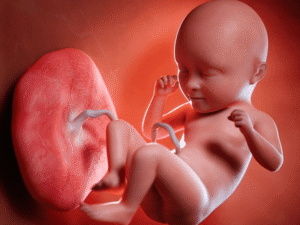

Nhau thai bám mặt trước là gì? Có nguy hiểm không?

Nhau thai bám mặt trước là tình trạng bánh nhau phát triển và bám vào ...

Nhau thai bám mặt trước có sao không? Cần lưu ý gì?

Nhiều mẹ bầu khi siêu âm thai kỳ thường nghe nhắc tới nhau thai bám ...